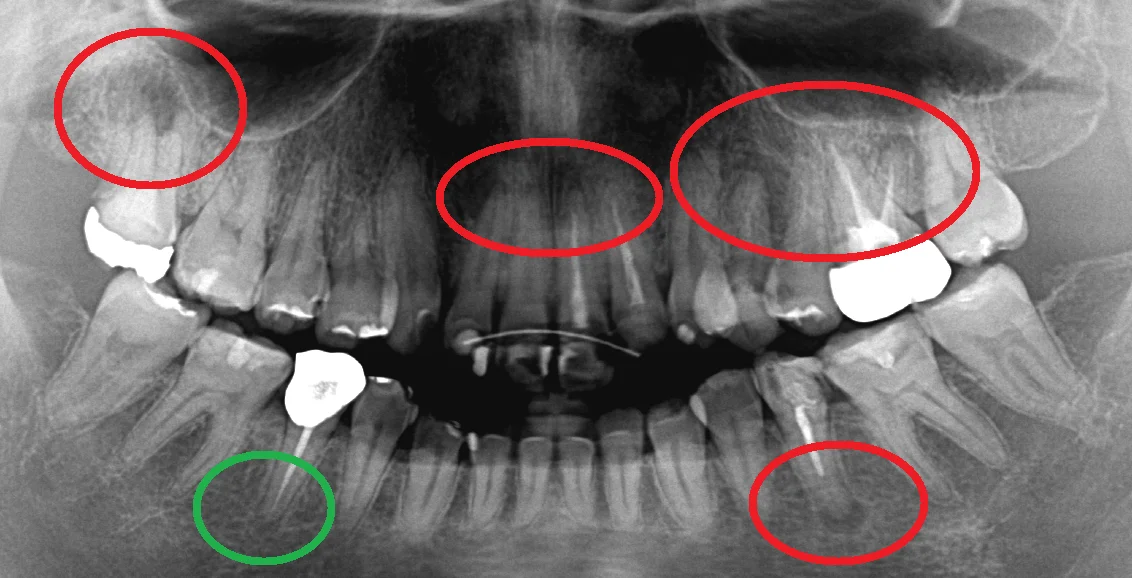

中心結節破折が原因で起こった神経の壊死を放置して、外部吸収が起こったケース

中心結節破折が原因で起こった神経の壊死を放置して、外部吸収が起こったケース

神経の治療⑤

こんにちは。 今回はまた神経の治療についてです。 40代の女性の方ですが、数年前から疲れた時に腫れたり膿が出たりしていたそうです。 定期検診を受けられていたとのことでしたが、レントゲン診査は随分としていないとのことです。...

続きを読む →